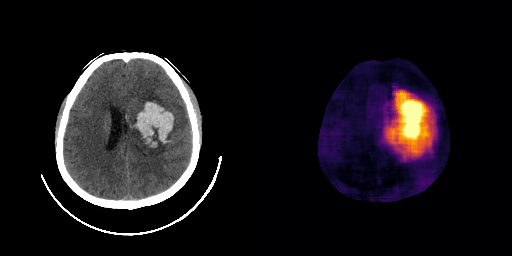

fig:qualitative_ich

ICH

healthy

We show some slices with examples of ICH in \figurereffig:qualitative_ich as well as surface renderings of scans of subjects with cranial fractures in \figurereffig:qualitative_fractures. (As a reference we also included the same examples for the AE in Appendix D in \figurereffig:qualitative_ich_ae.) It is noticeable that the reconstruction error is high where there is an anomaly. The reconstruction error generally seems to continuously depend on the amount of the patch that is anomalous, as the error maps generally seem to be rather smooth.

The performance for the models used for \figurereffig:qualitative_ich and LABEL:fig:qualitative_fractures are shown in \figurereffig:roc_performance. We observe see that the detection of fractures is the more challenging task for our method than the detection of ICH. This might be due to the smaller number of scans available to evaluate it on (see Appendix B). To put these results in context we provided a table with the inter rater agreement on these tasks in Appendix B: The performance in terms of AUROC is around lower than the average raters.